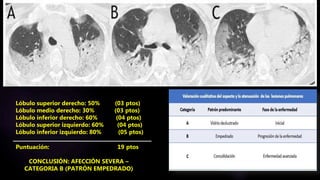

Lóbulo superior derecho: 50% (03 ptos)

Lóbulo medio derecho: 30% (03 ptos)

Lóbulo inferior derecho: 60% (04 ptos)

Lóbulo superior izquierdo: 60% (04 ptos)

Lóbulo inferior izquierdo: 80% (05 ptos)

Puntuación: 19 ptos

CONCLUSIÓN: AFECCIÓN SEVERA

CONCLUSIÓN: AFECCIÓN SEVERA –

CATEGORIA B (PATRÓN EMPEDRADO)